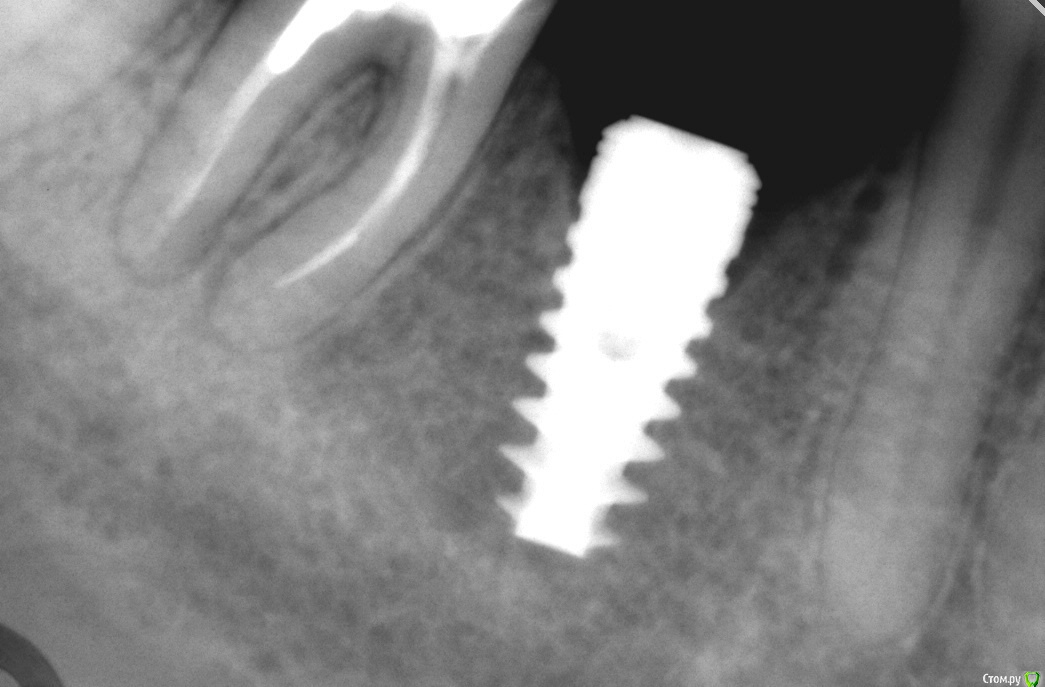

simpsons Опубликовано 22 января, 2016 Поделиться Опубликовано 22 января, 2016 Имплантация была год назад "Alfa Bio". Пац. вовремя не явилась. сегодня делаю снимок и вот... на десне возле заглушки образование в виде эпулиса. Какие варианты лечения? Ссылка на комментарий

КДБ Опубликовано 22 января, 2016 Поделиться Опубликовано 22 января, 2016 ревизия,формирователь,мягкотканная...и воздержаться от агрессивной резьбы Ссылка на комментарий

АнтонТЛТ Опубликовано 22 января, 2016 Поделиться Опубликовано 22 января, 2016 ревизия вместе с НКР или просто ревизия?Без нкр 1 Ссылка на комментарий

АнтонТЛТ Опубликовано 22 января, 2016 Поделиться Опубликовано 22 января, 2016 Хлоргексидин, фдм с метрогилом дента или гелем хлоргексидиновым. По поводу мягкотканной аугментации - сделать после исчезновения воспаления, если надо. 2 Ссылка на комментарий